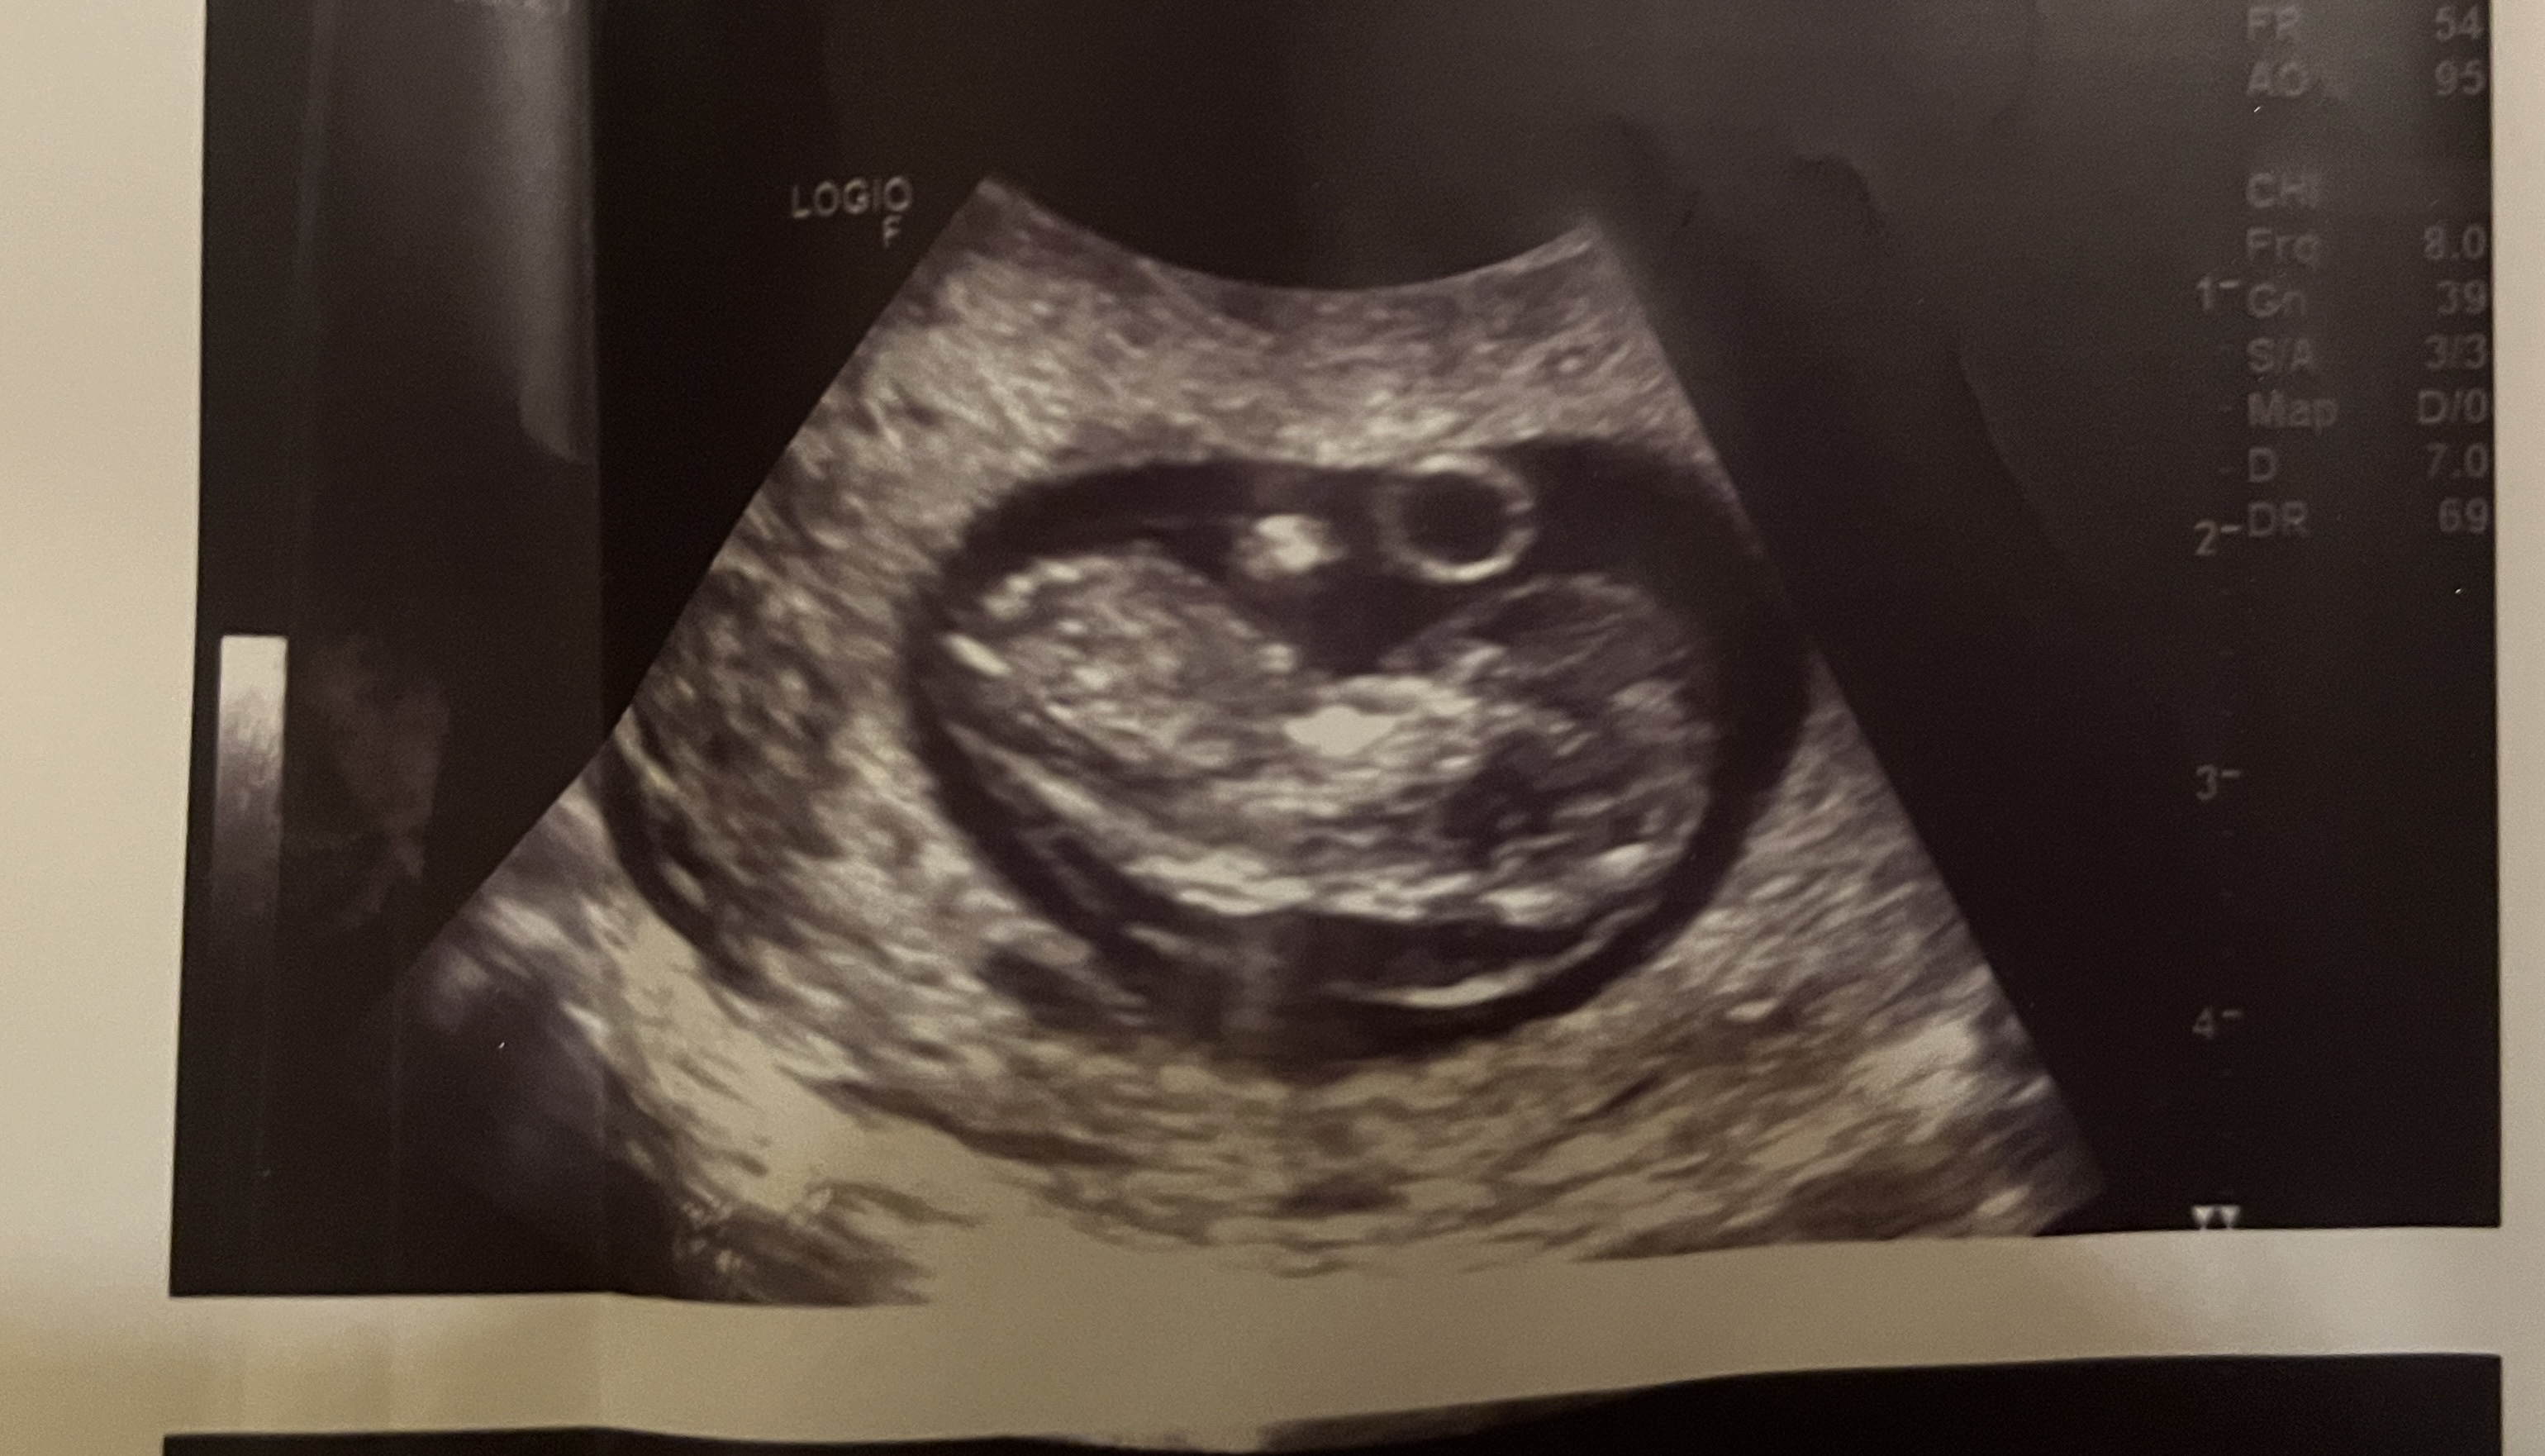

Witam! Mam podobny problem. Byłam na USG w poniedziałek i zdjęcie USG bardzo podobne. Podsyłam w załączniku. W poniedziałek idę na test Nifty, a za tydzień na badania prenatalne na NFZ. Czy możesz powiedzieć co okazało się przyczyna? Mam podobne odczucie - naczytałam się za dużo na temat obrzęku i bardzo się boję. Choć Twoja wiadomość bardzo mnie uskrzydliła! PozdrawiamJa w pierwszej ciąży w 10 tc na badaniu w luxmedzie też usłyszałam, że jest obrzęk - no i lekarka się mnie pytała, czy byłam chora/miałam jakieś infekcje. Akurat byłam zdrowa, więc przez 2 kolejne dni jak się naczytałam o obrzęku płodu to wiadomo, nie było za ciekawieJeszcze wyjeżdżałam na 2 tyg za granicę na urlop i nie miałam jak zrobić USG np za tydzień. Kolejnego dnia byłam na jeszcze jednym USG i ten obrzęk też był widoczny. Na dzień przed wyjazdem zrobiłam Nifty, wyniki przyszły pod koniec urlopu, że jest wszystko ok

poniżej moje USG z tego okresu.

Zobacz załącznik 1603751